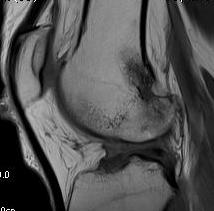

Coronal MRI can see ACL stump remnant, graft not intact. First sagittal confirms tunnel lysis.

Second demonstrates that femoral tunnel is sufficiently posterior